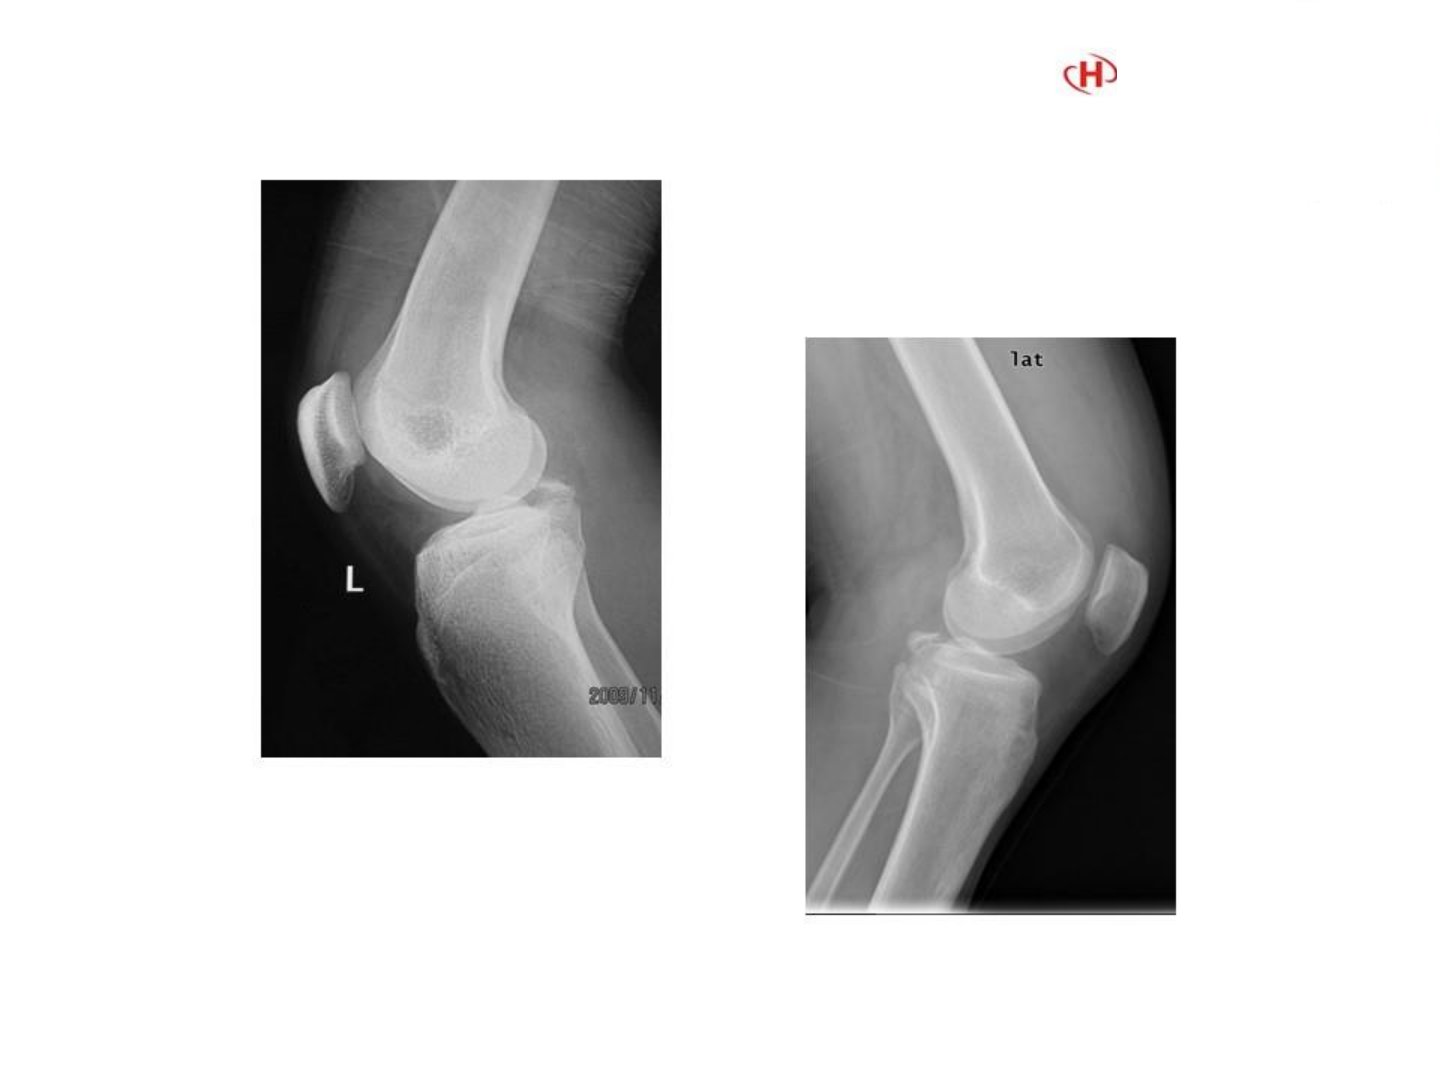

后交叉韧带胫骨止点撕脱骨折镜下复位固定技术摘要后交叉韧带胫骨止点撕脱骨折是膝关节常见损伤传统治疗手段存在一定局限性而镜下复位固定技术凭借其微创、精准等优势逐渐成为重要治疗方式。该技术借助关节镜设备能清晰呈现关节内结构精准定位骨折部位。术中医生通过小切口插入关节镜及配套器械对撕脱的骨折块进行细致复位恢复后交叉韧带胫骨止点的正常解剖结构。随后采用合适的内固定材料如空心螺钉、可吸收螺钉或带线锚钉等将骨折块牢固固定。此技术不仅减少了手术创伤降低术后感染等并发症风险还能促进骨折愈合及关节功能恢复。患者术后可早期进行康复训练有效缩短康复周期提高生活质量在临床上为后交叉韧带胫骨止点撕脱骨折患者提供了更优的治疗选择。